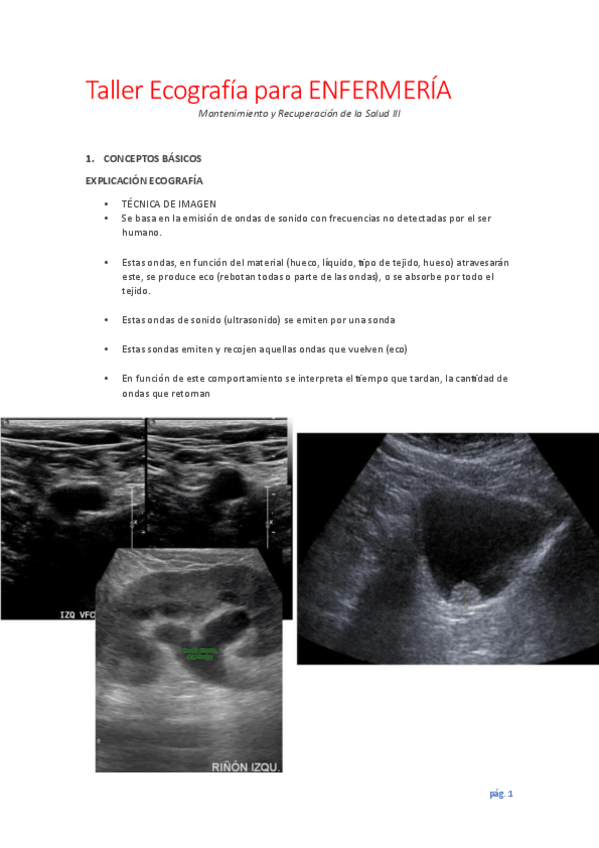

He publicado nuevos apuntes de 3º Mantenimiento y recuperación de la salud: Integración de procesos de cuidados III: Taller-Ecografia-para-ENFERMERIA.pdf